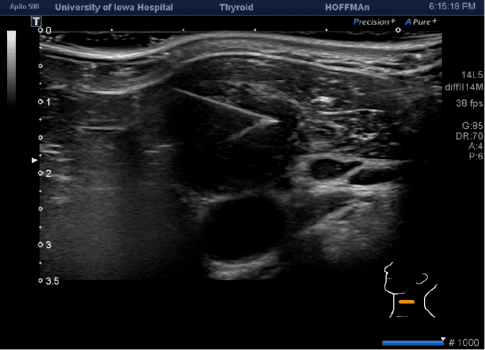

Steril koşullar sağlanarak, ultrason eşliğinde büyümüş lenf nodu içerisine girilip oradan vakum etkisi ile hücre örnekleri alınmaya çalışılır. Alınan örnekler patoloji labaratuvarına gönderilip patolojik tanı alınır. İşlem sonrasında hasta günlük işlerine devam edebilir, yatış gerekmez.